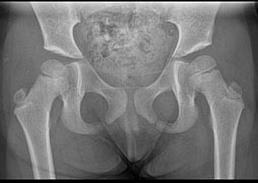

Omslagsbild: Gunnar Flivik. Bilden visar hur en stor del av ena bäckenhalvan hos en patient med kondrosarkom är utbytt mot en 3D-printad skräddarsydd protes.

Resultat: De nya ytersättningsproteserna introducerades av främst McMinn och Amstutz strax efter sekelskiftet 2000 och fick ett betydande genomslag, inte minst som protes för unga och aktiva ”idrottsprotes” (bild till höger). Rapporter om komplikationer med höga nivåer av metalljoner, destruerande

mjukvävnad runt leden (pseudotumör) och collumfrakturer började dock relativt snart påverka entusiasmen.

En av tillverkarna drog 2010 in sin protes med omedelbar verkan. Men nästan 100 000 patienter hade då redan blivit opererade med denna protes. Härefter har metoden snabbt minskat i användning – även om vissa ”entusiaster” fortsätter att genomföra operationen. De vetenskapligt verifierade riskerna med ytersättningsprotes är;

1. Avaskulär nekros av collum/caput (bild). Detta kan leda till fraktur på lårbenshalsen.

Röntgen av osteolys, caputnekros och collumfraktur samt en ytersättningsprotes infälld i bild.

2. Pseudotumör – som i vissa fall kan bli mycket stor och destruera benet runt leden. Pseudotumör har kopplats till ökade koncentrationer av metalljoner i vävnaden kring protesen och i blodet. Pseudotumörer kan förekomma både hos patienter som erhållit ytersättningsprotes och sådana som opererats med andra helproteser med stort metallhuvud kombinerat ledskål i metall.

3. Höga nivåer av cirkulerande metalljoner (krom och kobolt) från ledens ytor.

PET-CT av ytersättningsprotes 1 vecka, 4 månader och 14 månader efter operationen. Pilarna visar en gradvis utveckling av caputnekros i den opererade höften. Gösta Ullmark, Gävle.